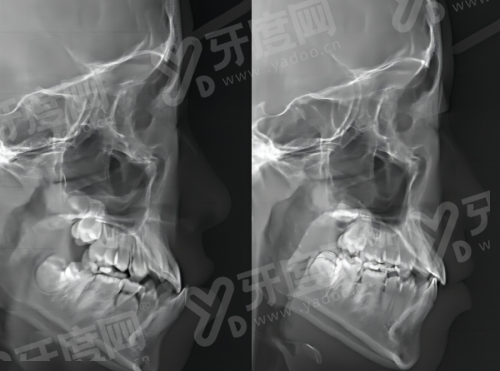

3、院内的设备都是比较新的,比如口腔CT机,能清晰看到牙齿和牙槽骨的情况,辅助医生更精细地操作,减少诊疗时间。